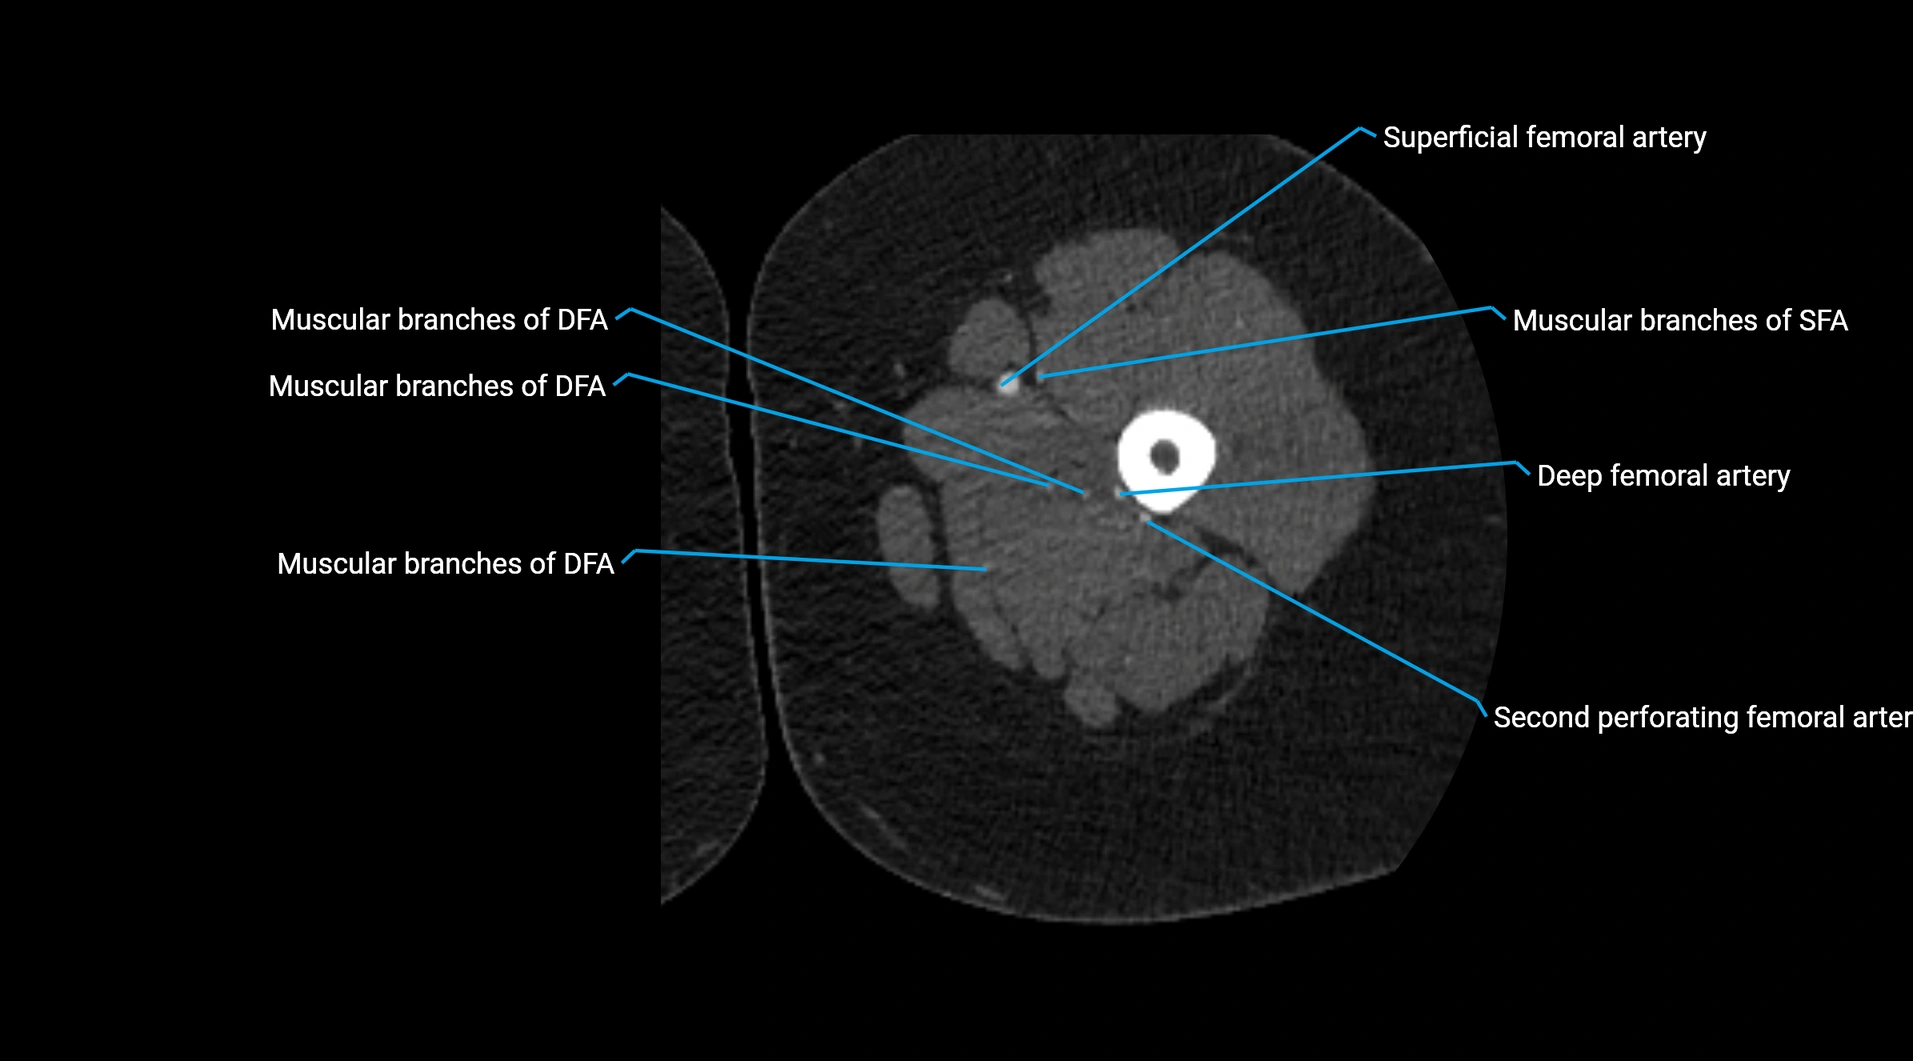

CT images

image